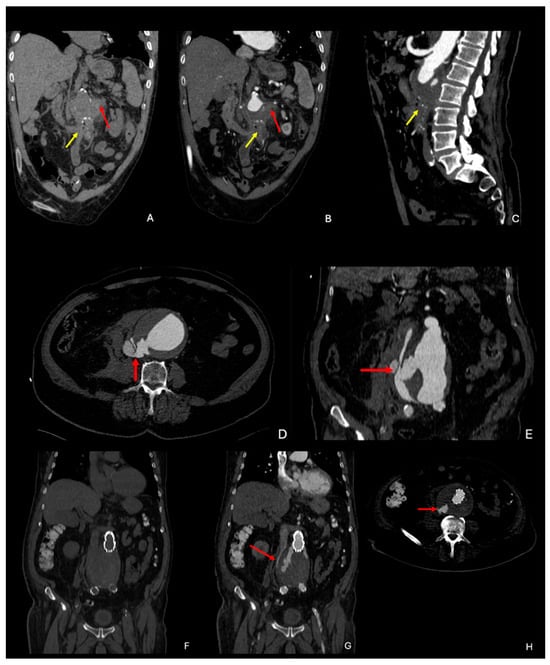

3. CTA Findings of Aneurysm Rupture

7.3. Endoleak

- Rakita, D.; Newatia, A.; Hines, J.J.; Siegel, D.N.; Friedman, B. Spectrum of CT Findings in Rupture and Impending Rupture of Abdominal Aortic Aneurysms. RadioGraphics 2007, 27, 497–507. [Google Scholar] [CrossRef]

- Schwartz, S.A.; Taljanovic, M.S.; Smyth, S.; O’Brien, M.J.; Rogers, L.F. CT Findings of Rupture, Impending Rupture, and Contained Rupture of Abdominal Aortic Aneurysms. Am. J. Roentgenol. 2007, 188, W57–W62. [Google Scholar] [CrossRef]